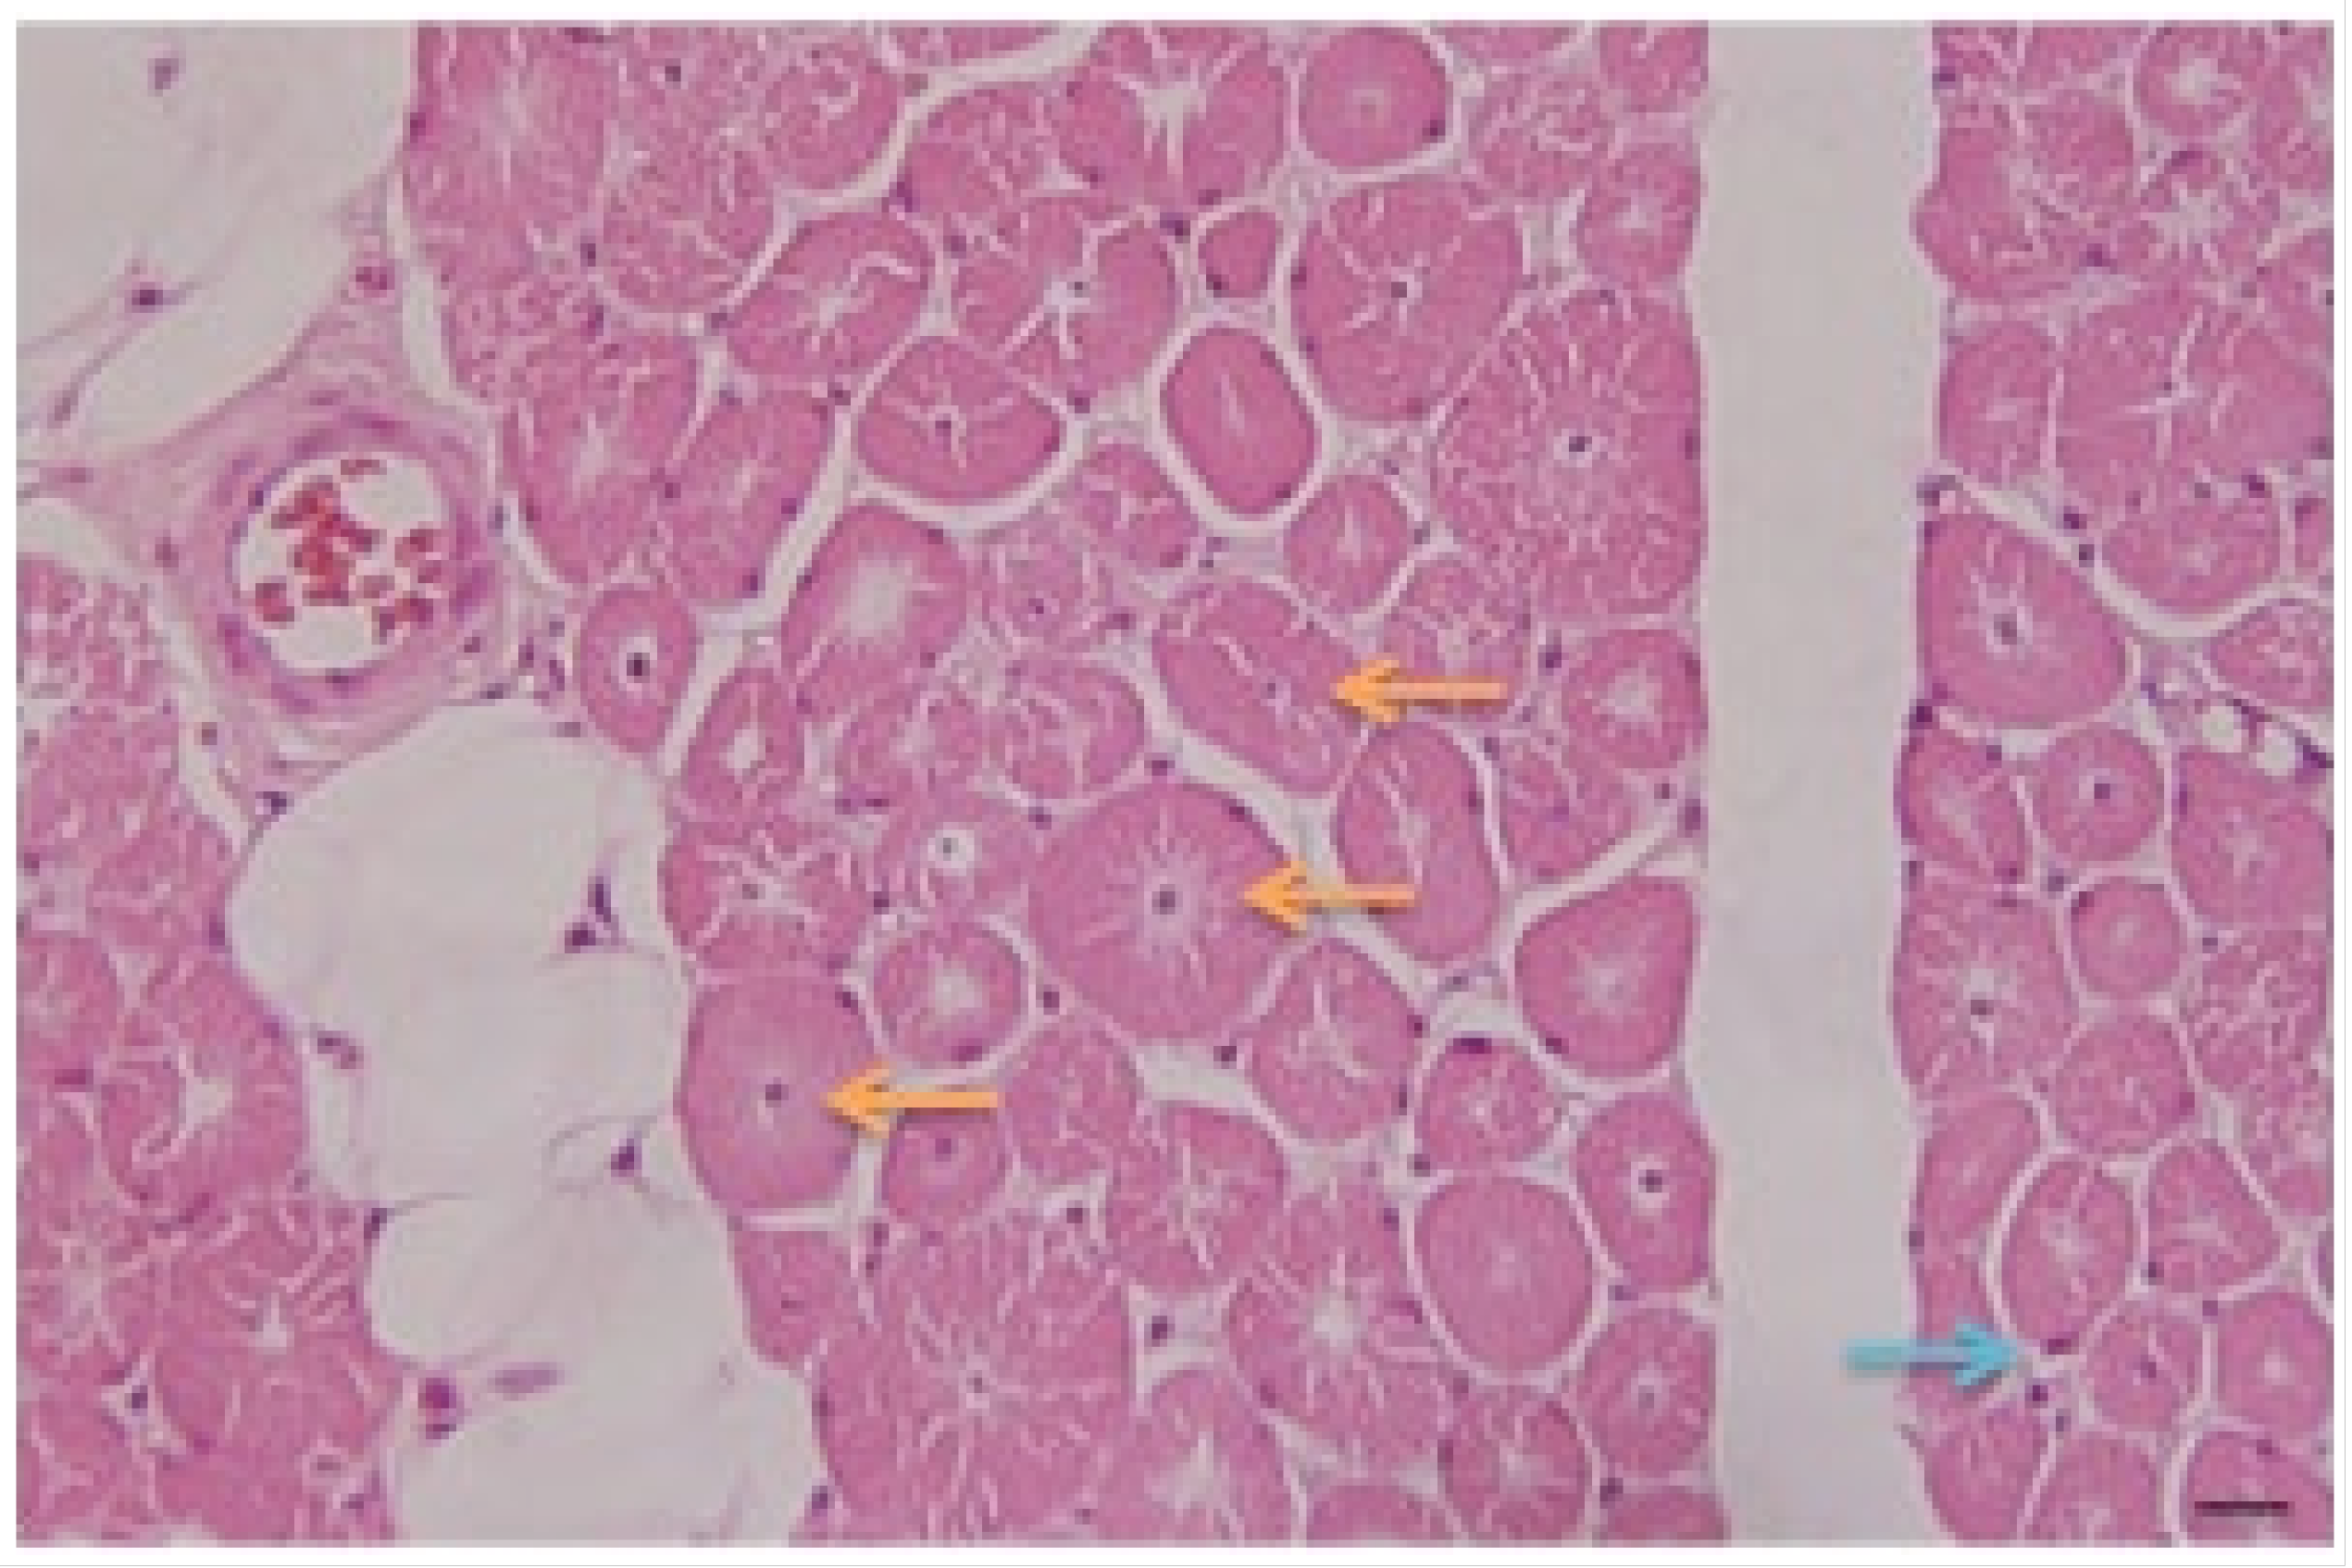

- Pathology: Biopsy of left deltoid striated muscle fragment was performed. The microscopic study of the studied fragments stained with hematoxylin–eosin (H/E) (Figure 3) and Masson’s trichrome showed:

- Presence of fibers with central nuclei;

- Presence of atrophic fibers;

- Fibers of normal diameters and some hypertrophic ones;

- Presence of clear perinuclear spaces and others with multiple central tunnels as an expression of myofilament loss;

- No inflammation or macrophage phenomena were observed;

- No increase in connective tissue is appreciated;

- Discrete fatty infiltration in the perimysial center.